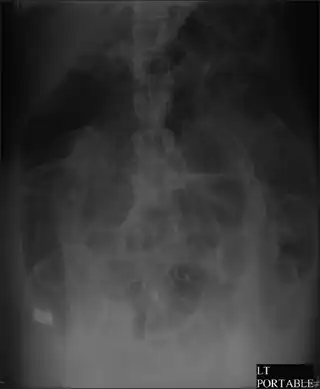

| CT scan of the abdomen of an elderly woman with Ogilvie syndrome | |

It generally occurs in those with significant health problems or following surgery.[2][1] While the underlying mechanism is unclear, it is believed to involve poor contraction of the colon.[3][1] Generally the cecum has a diameter of more than 10 cm and right colon is also dilated.[4] A CT scan or water-soluble enema is done to rule out a obstruction.[1]

Diagnosis starts with physical exam, observation, and interview of the patient. Imaging to diagnose dilation of the colon involves one view abdominal xray or obstruction series (PA chest, erect abdomen, and supine abdomen images). If further imaging is needed CT may be ordered.[13]